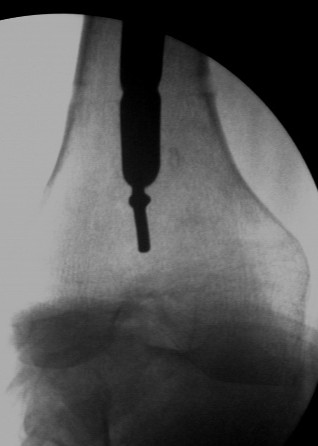

with the knee flexed. Pass the k wire into the lumen of the nail for a short distance. I am not sending the pictures to you to prepare a composite one, rather, send 3 or 4 mails each including one picture.

VMI-I am enclosing pictures of how I had to do it once. The C arm picture shows the first attempt to try and jam a solid reamer into the nail and trying to pull it out. Did not work.

The second picture shows a plain guide wire inserted thro the nail, prograde, hammered out thro the distal femur, out thro the skin. A beaded guide wire being railroaded on the earlier G W into the distal end of the nail.

This is the C-arm picture before attemting to pull out thro the proximal end by hammering on a chuck.

Did not work out. The nail was a slotted one. The guidewire split the slot and came out but not the nail. Ultimately as mentioned in an earlier mail, I had to introduce a cannulated nail from distally threadind on the guide wire and hammer on the stuck nail and finally got it out